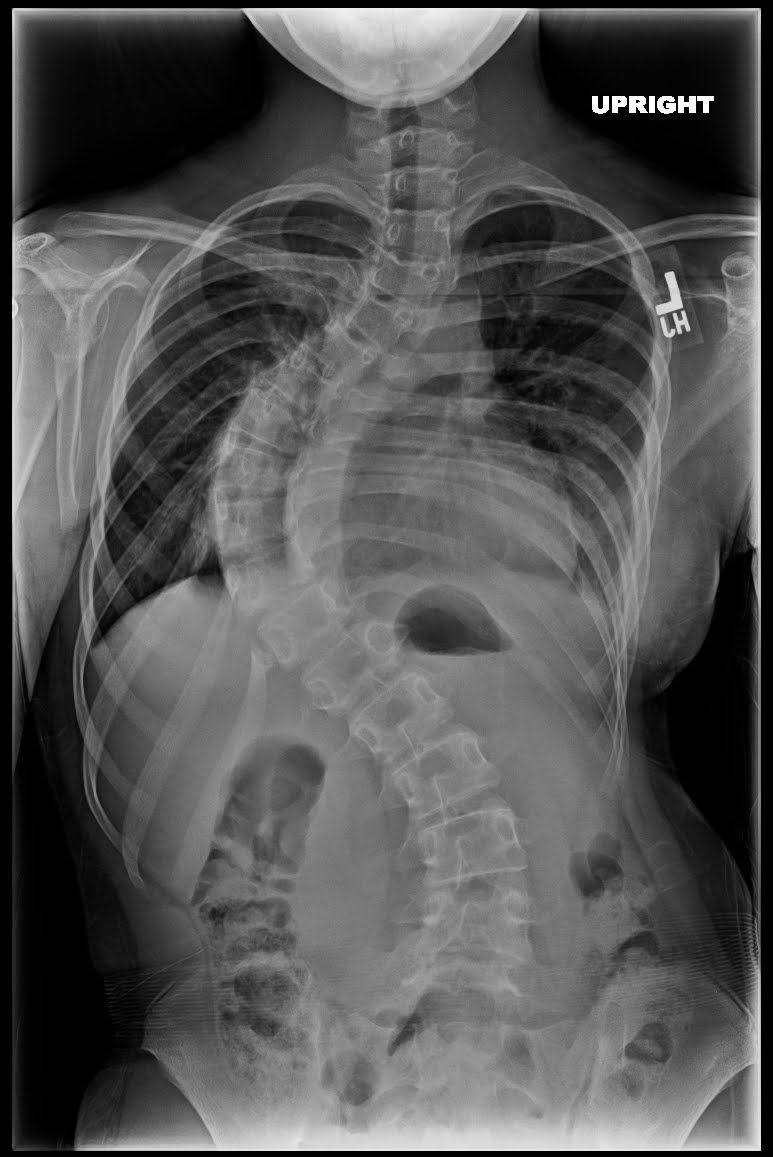

وبصفة عامة فإن الانحناءات التي تتراوح بين ال25 و ال50 درجة يتم اعتبارها كبيرة إلى حد ما بحيث تحتاج إلى العلاج. وبالنسبة للانحناءات التي تزيد عن 50 درجة فسوف تحتاج إلى الجراحة للحصول على الشكل السليم للوضعية

يطرح الطبيب المعالج خيار الجراحة عندما تكون درجة الانحناء أكثر من 45 درجة في مرحلة النمو او اكبر من 50 درجة في مرحلة ما بعد النمو